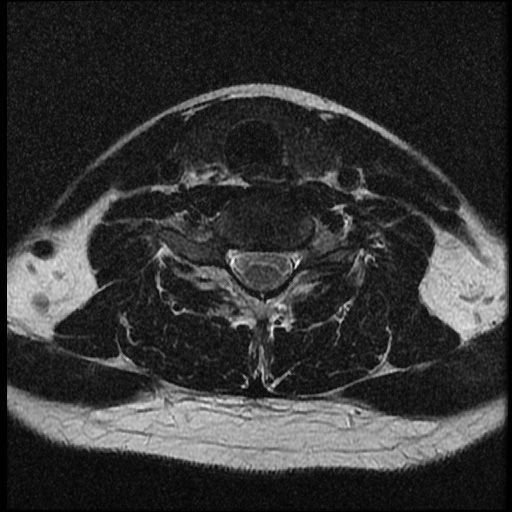

이 MRI 사진은 21년도 사고 당시 찍은 MRI 사진 입니다. 확인 부탁드립니다~

전체 mri를 다 봐여겠지만 보여주신 mri 컷에서는 의미있는 경추 디스크탈출이 보이지 않습니다.